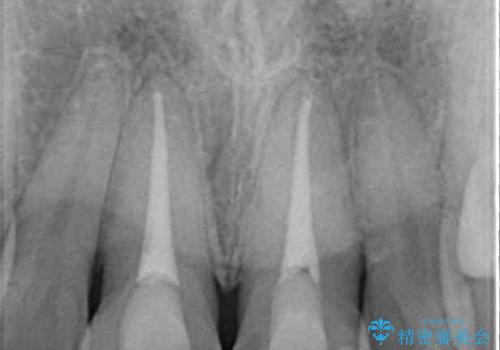

- 神経を取り除いたことで経年変色した前歯2本を気にして来院された患者様です。

根管治療を行う必要はないと判断し、双方の歯にグラスファイバーを含有した土台を植立してオールセラミッククラウンにて補綴することとしました。